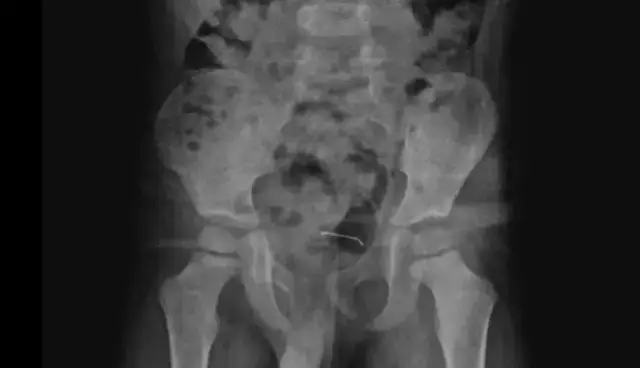

Karın ağrısı şikayeti bulunan çocuğun çekilen röntgeninde, mesane duvarında metal cisim olduğu tespit edildi. Uzun süre vücutta kalan 3 santimetre civarındaki toplu iğnenin, mesane duvarına yapıştığı belirlendi. Ailenin bilgilendirilmesinin ardından Çocuk Cerrahi Uzmanı Op. Dr. Tahsin Onat Kamçı tarafından ameliyata alınan çocuğun yuttuğu toplu iğne çıkarıldı.

Kamçı, 5 yaşındaki hastanın 9 ay önce cisim yuttuğunu ancak ailenin bunun toplu iğne veya çivi olduğunu ayırt edemediğini söyledi. Hastanın kontrollerinde, yuttuğu cismin doğal yollarla vücuttan çıkmadığını tespit ettiklerini anlatan Kamçı, "Bunun üzerine ameliyat kararı aldık. Ameliyatta cismin mesane duvarına yapıştığını gördük. Cerrahi operasyonla 3 santimetre civarındaki toplu iğneyi çıkardık. Hastayı birkaç gün takipte tuttuk. Genel sağlık durumu iyi olan hastamızı taburcu ettik." diye konuştu.